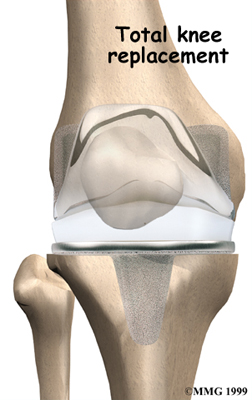

Artificial Knee Replacement

An artificial knee replacement is the ultimate solution for advanced knee OA.

Surgeons prefer not to put a new knee joint in patients younger than 60. This is because younger patients are generally more active and might put too much stress on the joint, causing it to loosen or even crack. A revision surgery to replace a damaged prosthesis is harder to do, has more possible complications, and is usually less successful than a first-time joint replacement surgery.

Related Document: FYZICAL Falcon's Guide to Artificial Joint Replacement of the Knee